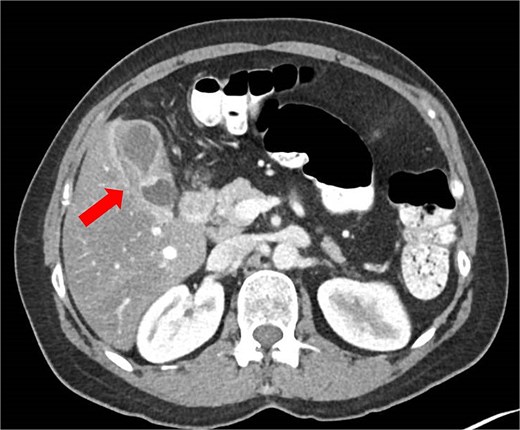

Histological evaluation revealed a 2.7 cm moderately differentiated ASC with extensive necrosis (Fig. 2), perimuscular connective tissue invasion, and lymphovascular involvement. Immunohistochemistry was positive for p40, confirming squamous differentiation (Fig. 3). All surgical margins were uninvolved, and three examined lymph nodes were negative. The tumour was staged as pT2aN0 based on the American Joint Committee on Cancer (AJCC) 8th edition criteria [11].

Magnified view (haematoxylin and eosin stain, ×10) of the gallbladder showing mucin glands related to the adenomatous component (narrow arrow) and solid features including stromal infiltration of the squamous components (thick arrow).